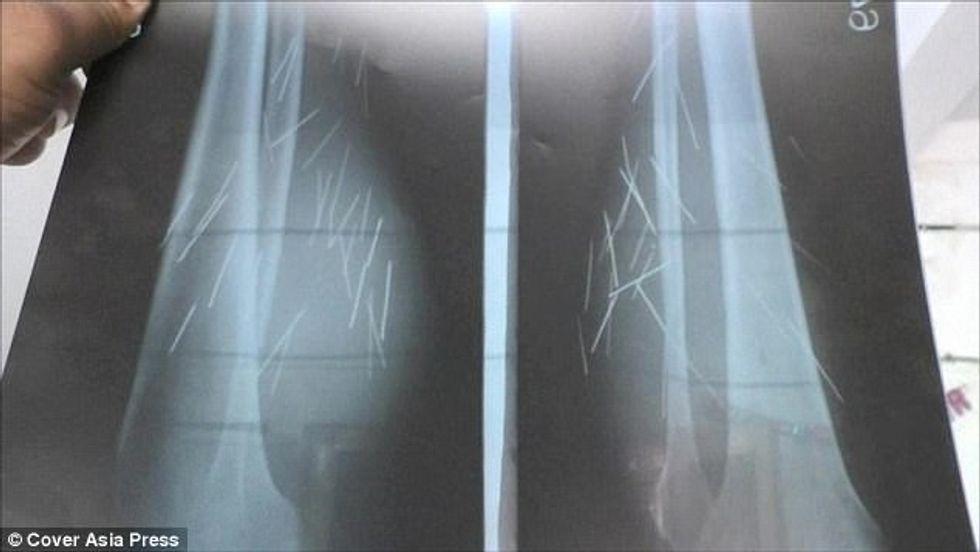

Anusuiya Devi nga Uttar Pradesh i Indisë, nxjerrë shpesh nga këmba gozhda dhe shiringa, ndërsa nuk di se si i kanë përfunduar aty.

Derisa 35-vjeçarja nuk pranon se i ka futur vet, apo vetëlënduar, mjekët nuk dinë si të shpjegojnë gjendjen e saj në të cilën ndodhet prej vitit 2012, transmeton Telegrafi.

Ajo pretendon se i paraqiten puçrra, prej të cilave i dalin objektet e mprehta metalike.

Psikologët kanë thënë se ajo ka gjendje të mirë mentale dhe nuk po gënjen, ndërsa mbetet mister gjetja e 70 objekteve metalike që i kanë dalë deri tani nga këmbët.